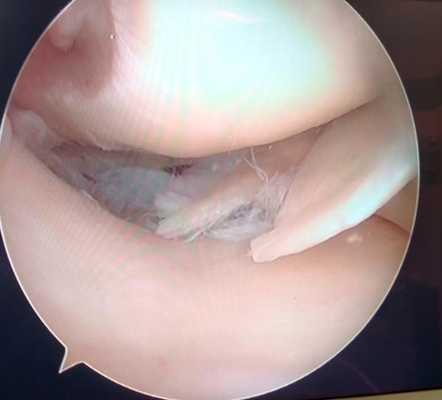

Дегенеративный комбинированный разрыв тела и заднего рога внутреннего мениска коленного сустава.

Продольный разрыв заднего рога наружного мениска, сопровождающийся его гипермобильностью. При таком разрыве мениск может значительно смещаться внутрь сустава создавая ощущение механического блока, инородного тела, нестабильности в суставе, заклинивания, щелчков.

Мениск после обработки по поводу паракапсулярного субтотального разрыва по типу ручки лейки.